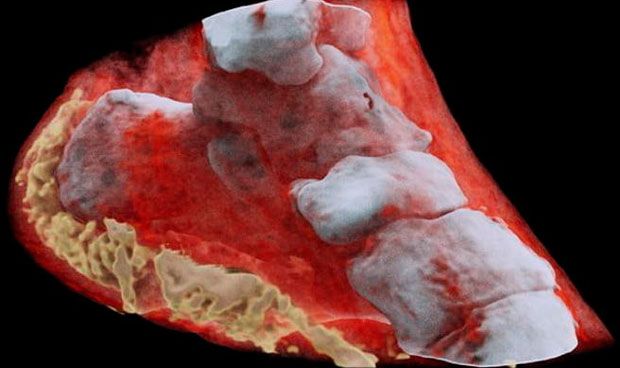

Una empresa de Nueva Zelanda ha desarrollado un nuevo tipo de escáner que permite realizar radiografías en 3D y a color. Este método se basa la tecnología de rastreo de partículas que se utiliza en el Large Hadron Collider, el acelerador de partículas del CERN.

Esta nueva tecnología podría utilizarse para obtener imágenes más detalladas y precisas que las radiografías tradicionales en blanco y negro y contribuir, de esta manera, a un mejor diagnóstico médico. Las primeras radiografías a colores que se han presentado públicamente muestran el detalle de un tobillo y una muñeca en la que se puede ver incluso el reloj.

El escáner, desarrollado por los científicos Phil y Anthony Butler de las Universidades de Canterbury y Otago en Nueva Zelanda, utiliza un detector que capta la información espectral, es decir, la información de color o energía de los rayos X que los detectores tradicionales no utilizan.

El chip Medipix3 funciona de forma similar al sensor de una cámara digital, pero cuando se abre su obturador es capaz de detectar y contar las partículas que golpean cada píxel.

Este chip, mejorado con algoritmos de procesamiento de datos personalizados, puede detectar el cambio en las longitudes de onda a medida que los rayos X pasan a través de diferentes materiales en el cuerpo. De esta manera el escáner puede distinguir entre hueso, músculo, grasa, líquidos y el resto de materiales y tejidos del cuerpo humano.

El software adicional que acompaña el escáner se basa en toda esa información para crear imágenes a todo color que permiten una visión tridimensional del interior de nuestro cuerpo.

Primeros resultados

Las primeras pruebas realizadas con este escáner ya se están utilizando para estudiar el cáncer, así como la salud ósea y articular en pacientes. Según sus impulsores, esta tecnología también será útil en otros campos médicos, desde odontología hasta la cirugía cerebral.